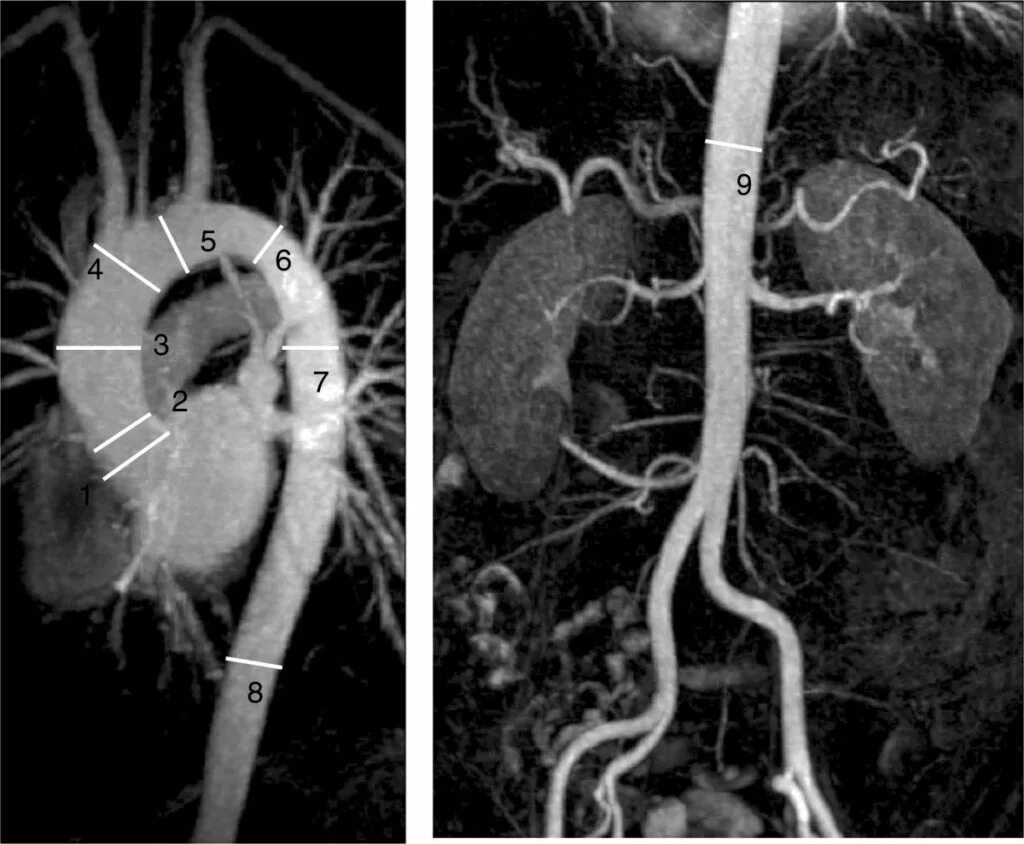

Тромбоз аневризмы аорты